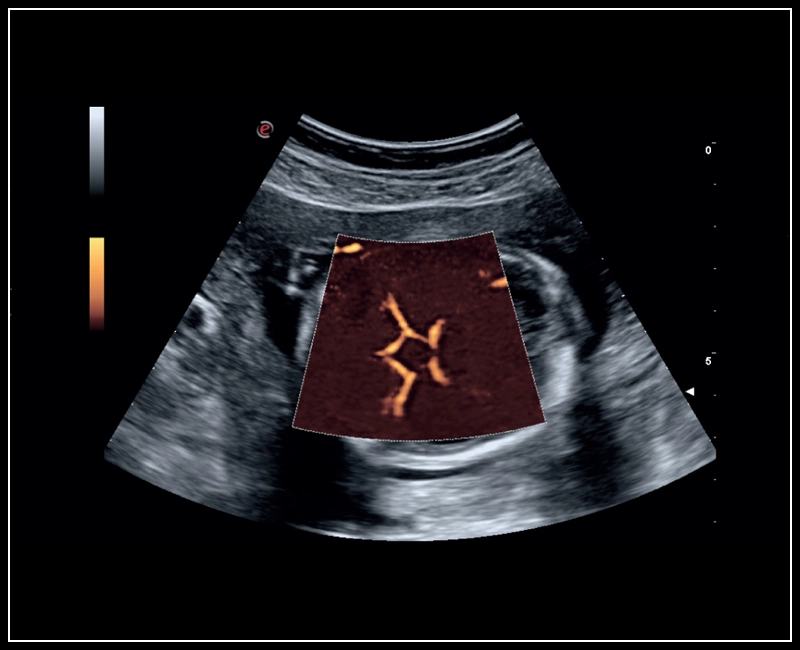

MyLab™E80 - microV - Kidney

MyLab™E80 - microV - Kidney

MyLab™9 Platform - Hemodynamics analysis using microV on kidney

MyLab™9 Platform - Hemodynamics analysis using microV on kidney

MyLab™Sigma - Kidney perfusion with high sensitivity Color Doppler mode

MyLab™Sigma - Kidney perfusion with high sensitivity Color Doppler mode

MyLab™A50 - microV kidney

MyLab™A50 - microV kidney